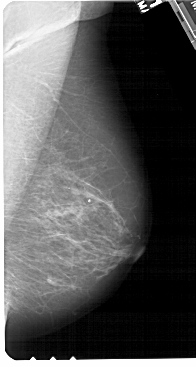

A_1442_1.RIGHT_MLO

RIGHT_MLO LINES 5491 PIXELS_PER_LINE 2926 BITS_PER_PIXEL 12 RESOLUTION 43.5 NON_OVERLAY